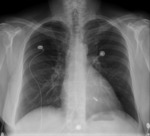

W Instytucie Kardiologii od dłuższego czasu wykorzystuje się dwie techniki przezcewnikowe, które mają uszczelnić czynnościową niedomykalność zastawki. Jedna z nich – system MitraClip – została wprowadzona do leczenia i ma odpowiednie certyfikaty (ryc. 1).

– W tej chwili mówimy o czynnościowej niedomykalności mitralnej, która jest wtórna do uszkodzenia lewej komory serca, najczęściej po zawale, i wymaga u tej grupy chorych innego podejścia – mówi prof. dr hab. Marcin Demkow. – Metoda opiera się na sczepieniu płatków zastawki mitralnej swego rodzaju klipsem wprowadzonym przezżylnie. Zabieg prowadzi do wytworzenia dwuujściowej zastawki mitralnej na wzór techniki znanego włoskiego chirurga Ottavio Alfieriego. Zabieg wykonuje się w pracowni hemodynamicznej, wykorzystując trójwymiarową echokardiografię przezprzełykową i fluoroskopię (ryc. 2).

Ryc. 2. Echokardiografia przezprzełykowa: klips MitraClip założony na płatki zastawki („brzeg do brzegu”) zmniejsza falę zwrotną.

– Już teraz widzimy u chorych poprawę w stosunku do pierwotnej sytuacji – ocenia prof. Hryniewiecki. Po połączeniu dwóch płatków zastawki mitralnej (sklipsowaniu), mniej więcej w części środkowej, powstaje wspomniana dwuujściowa zastawka. Dzięki temu krew mniej się cofa. To nie jest sytuacja idealna, ale chorzy odczuwają poprawę. Metoda została pozytywnie oceniona w badaniach EVEREST I i EVEREST II (Endovascular Valve Edge-to-Edge REpair STudy).